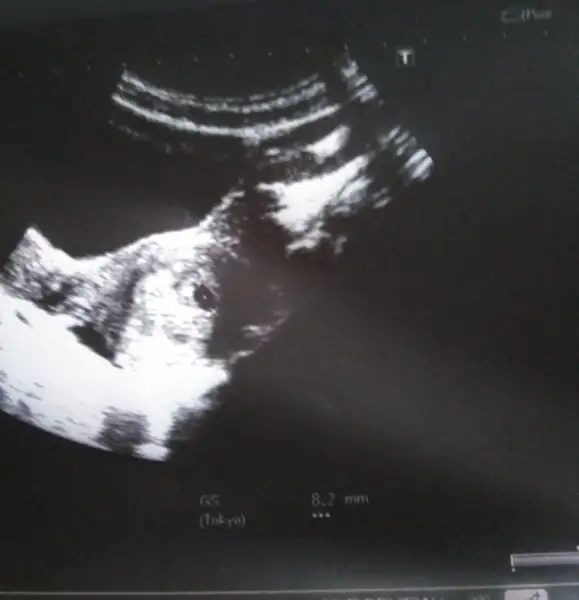

Oy oy oy maşallah minicik kesenin görmüşsün gözün aydın darısı bebeği görüp kalp atışını duymaya inşallahAy çok şükür buldum kızlar yaa bakın daha minicik 8mm ya doktor bir sıkıntı yok dedi kesenin yapısı düzgün kanama alanı falnda yokmuş kalp atışları için 2 hafta sonra gel dedien yakın zamanda kalp atışlarıni duyarz inslh..

tekrar hayırlı olsun canım. ben gelecek hafta gitcem. iki hafta çok uzun geliyor bana :)Ay çok şükür buldum kızlar yaa bakın daha minicik 8mm ya doktor bir sıkıntı yok dedi kesenin yapısı düzgün kanama alanı falnda yokmuş kalp atışları için 2 hafta sonra gel dedien yakın zamanda kalp atışlarıni duyarz inslh..

Kesenin icinde ki minik nokta da bebegin cnm olusmaya baslamis bnm kese fotomda boyleydi bebek olusmaya baslamis demisti drmAy çok şükür buldum kızlar yaa bakın daha minicik 8mm ya doktor bir sıkıntı yok dedi kesenin yapısı düzgün kanama alanı falnda yokmuş kalp atışları için 2 hafta sonra gel dedien yakın zamanda kalp atışlarıni duyarz inslh..

Hersey yolunda olsun da gec gorsen de zarari yok canim. Ben bugun gidemedim yarin ogleden sonraya randevu bulursam gidicemKızlar keseyi gorduk bebeği goremedk daha çok kücük dedi doktor 4 haftalk ancK var dedi sanırm gec döllenme kese 8mmZanamm174